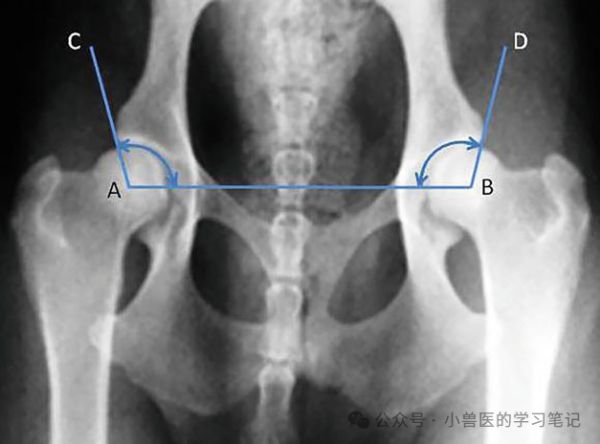

为了更客观地评估髋关节松弛度,不同的方法已经被使用。Norberg角(NA)以度数衡量,是由连接股骨头中心的直线和从股骨头中心到髋臼边缘的前外侧缘的直线所形成的角度(图9.11)。这有助于量化股骨头相对于髋臼的位置。尽管不同犬种的正常颈干角(NA)可能有所不同,但一般认为105°或以上的角度是正常的。全球有三种不同的评分系统用于量化犬髋关节发育不良的X光片变化。国际畜犬联盟(FCI)系统在大多数欧洲国家、南美、俄罗斯和亚洲的80多个国家中使用;动物矫形基金会(OFA)评分系统专门在美国和加拿大使用,而英国兽医协会/犬舍俱乐部(BVA/KC)系统则在英国、爱尔兰、澳大利亚和新西兰使用。

图 9.11 通过测量股骨头中心之间的连线(A-B)与从股骨头中心到髋关节缘的外侧缘连线(A-C 和 B-D)之间形成的角度(以度为单位)来诊断髋关节发育不良。